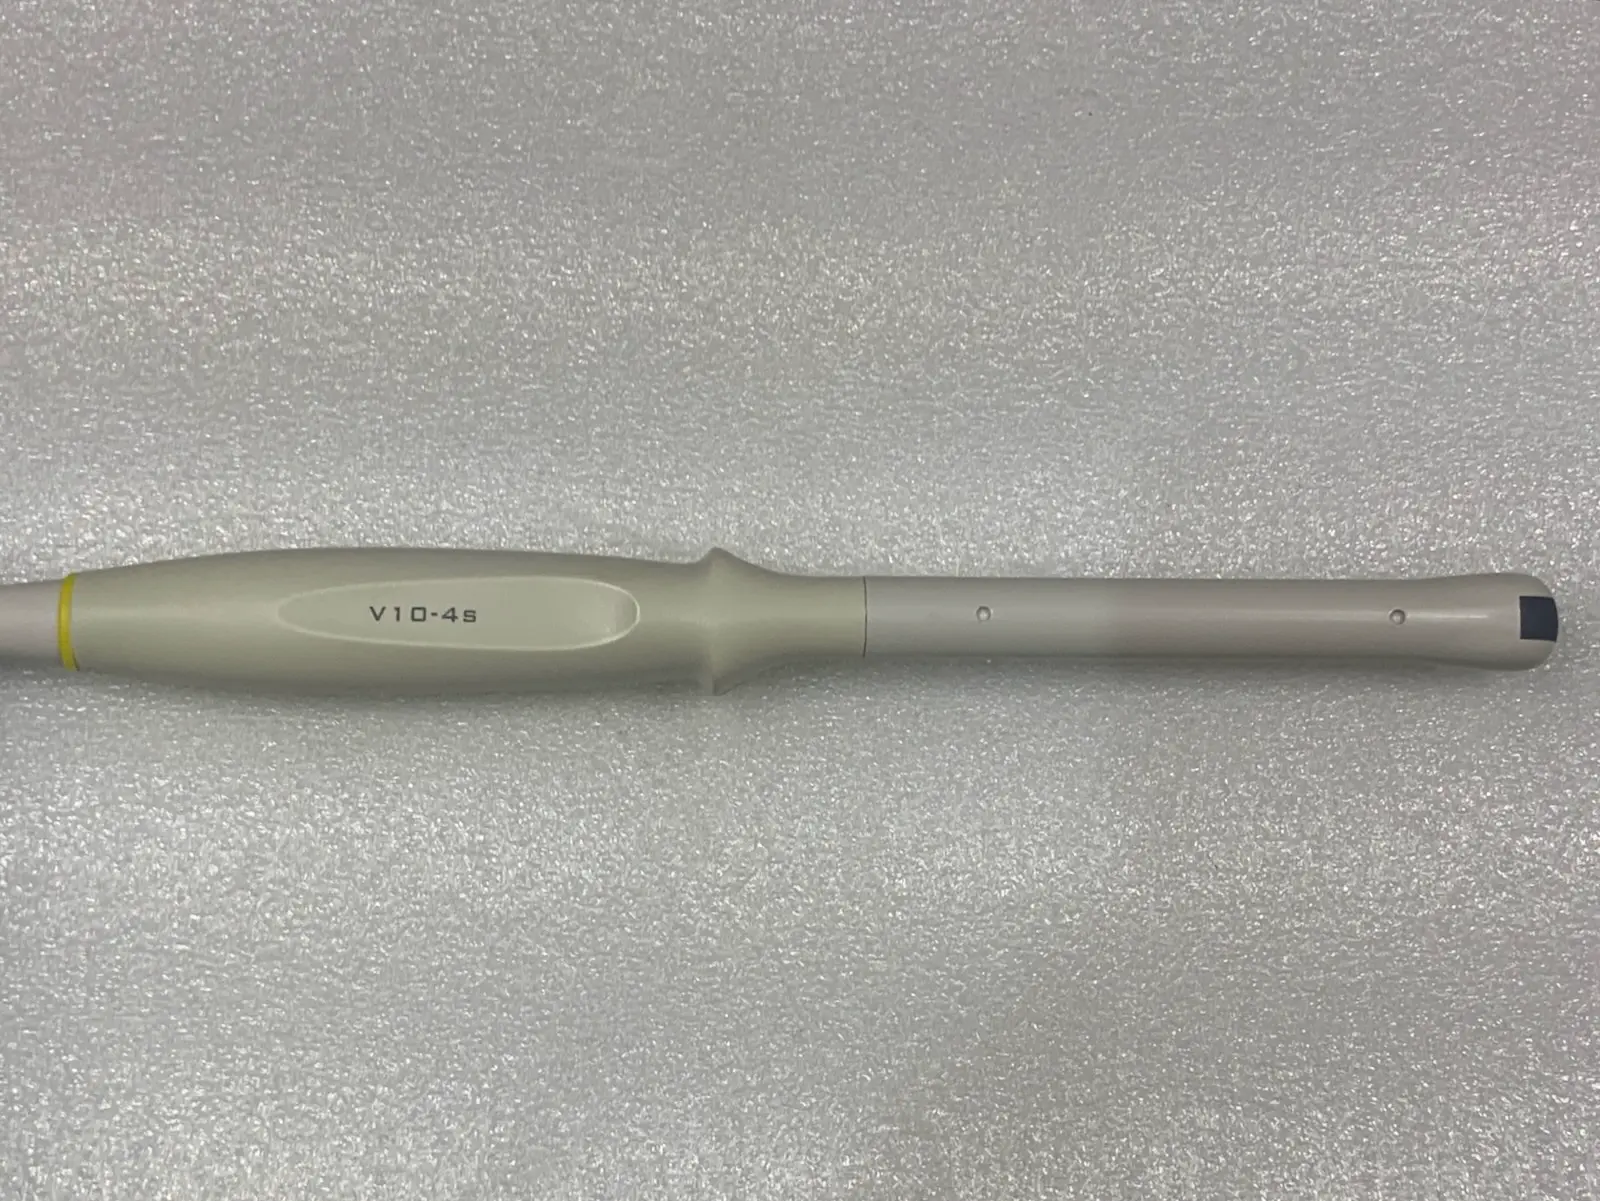

Brand: Mindray

Model: V10-4s

Probe Type: Endocavity / Transvaginal / Micro-convex

Frequency Range: 4.0 MHz – 10.0 MHz

Up for sale is a genuine Mindray V10-4s curved array endocavity probe. This transducer is designed for high-resolution imaging in obstetrics, gynecology, and urology. It features a wide-band frequency range (4–10 MHz) and a small 10mm radius for patient comfort.

Cable & Connector: The cable is flexible without exposed shielding; the connector pins are straight and the locking lever is functional.

Photos of this listing are of the actual item for sale.